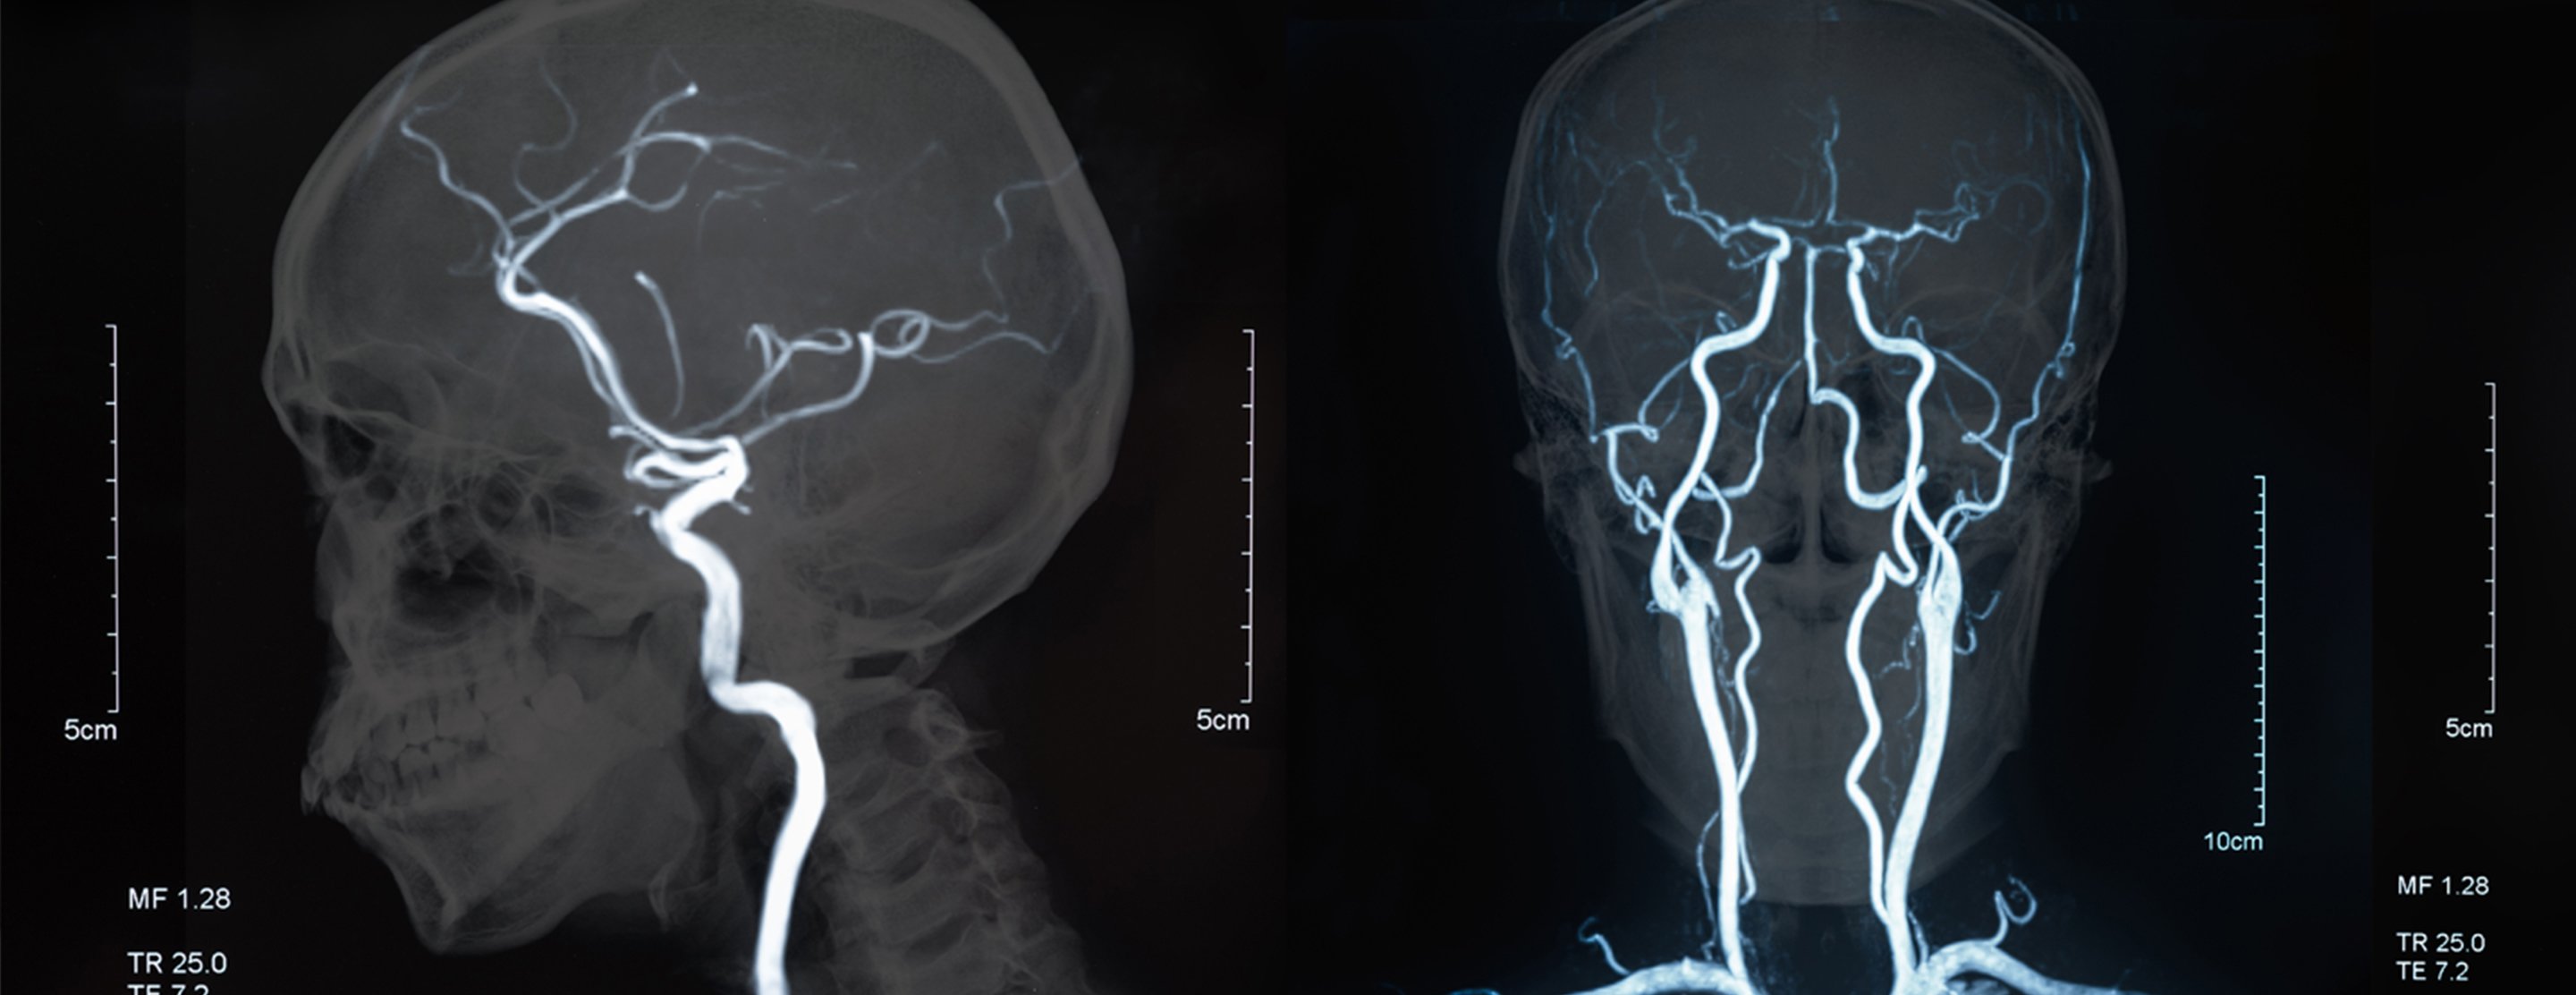

Magnetic resonance angiography

Magnetic resonance angiography (MRA) is an

MRA is used to look at the blood vessels in all parts of the body. The test may be done for the head, heart, abdomen, lungs, kidneys, and legs.